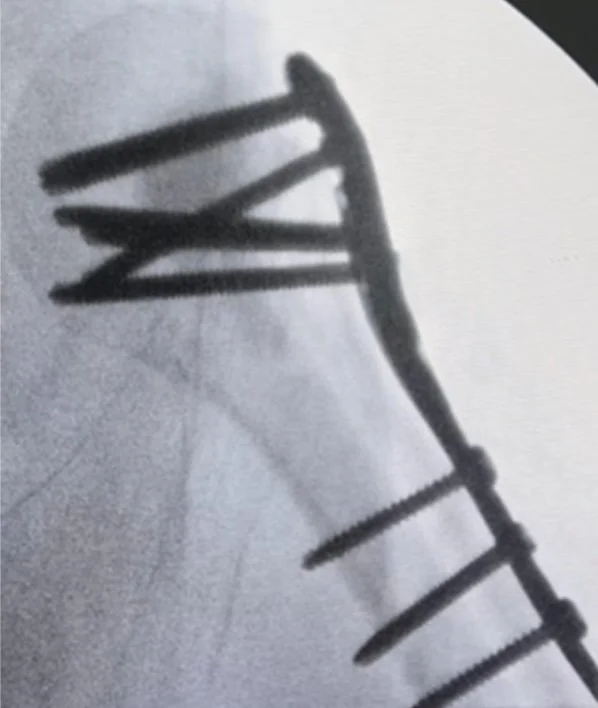

O estudo publicado na Cureus em janeiro de 2025 avaliou 30 pacientes idosos com fraturas do úmero proximal em três e quatro partes tratados com placas bloqueadas e enxerto sintético de sulfato de cálcio (CaSO₄). Após 12 meses de acompanhamento, os escores funcionais (Constant-Murley, UCLA e ASES) foram satisfatórios, com arco médio de flexão de 121° e abdução de 109°.

A consolidação foi obtida em todos os casos, e a taxa de complicações foi baixa (13,3%), principalmente colapso em varo e cut-out dos parafusos. O estudo demonstra que a associação entre placa bloqueada e enxerto sintético oferece resultados estáveis e reprodutíveis no tratamento de fraturas complexas do úmero proximal em idosos.